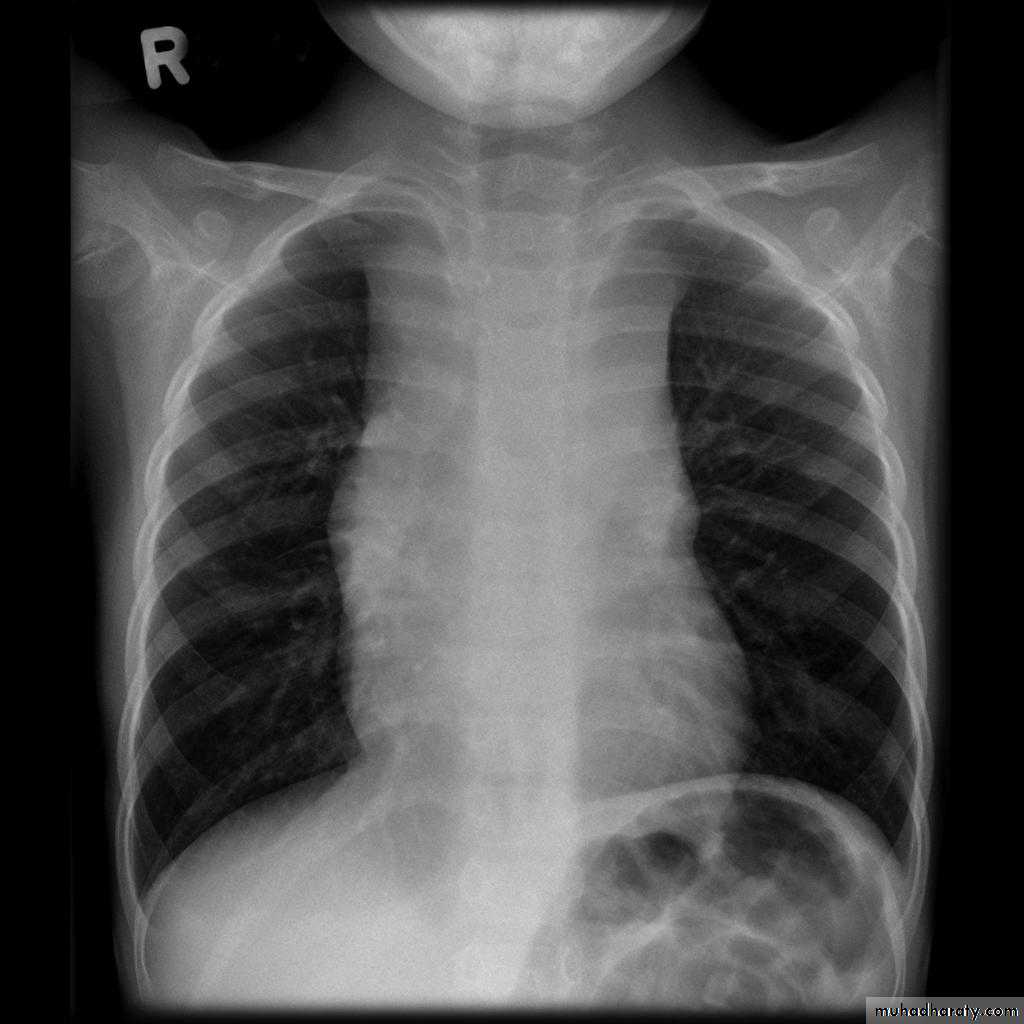

Radiographic features

Plain film "boot shaped" heart ( TOF )

Plain films may classically show :

1. "boot shaped" heart with an upturned cardiac apex due to right ventricular hypertrophy and concave pulmonary arterial segment.

2.Pulmonary oligaemia due to decreased pulmonary arterial flow.

3.Right sided aortic arch is seen in 25%.

TOF